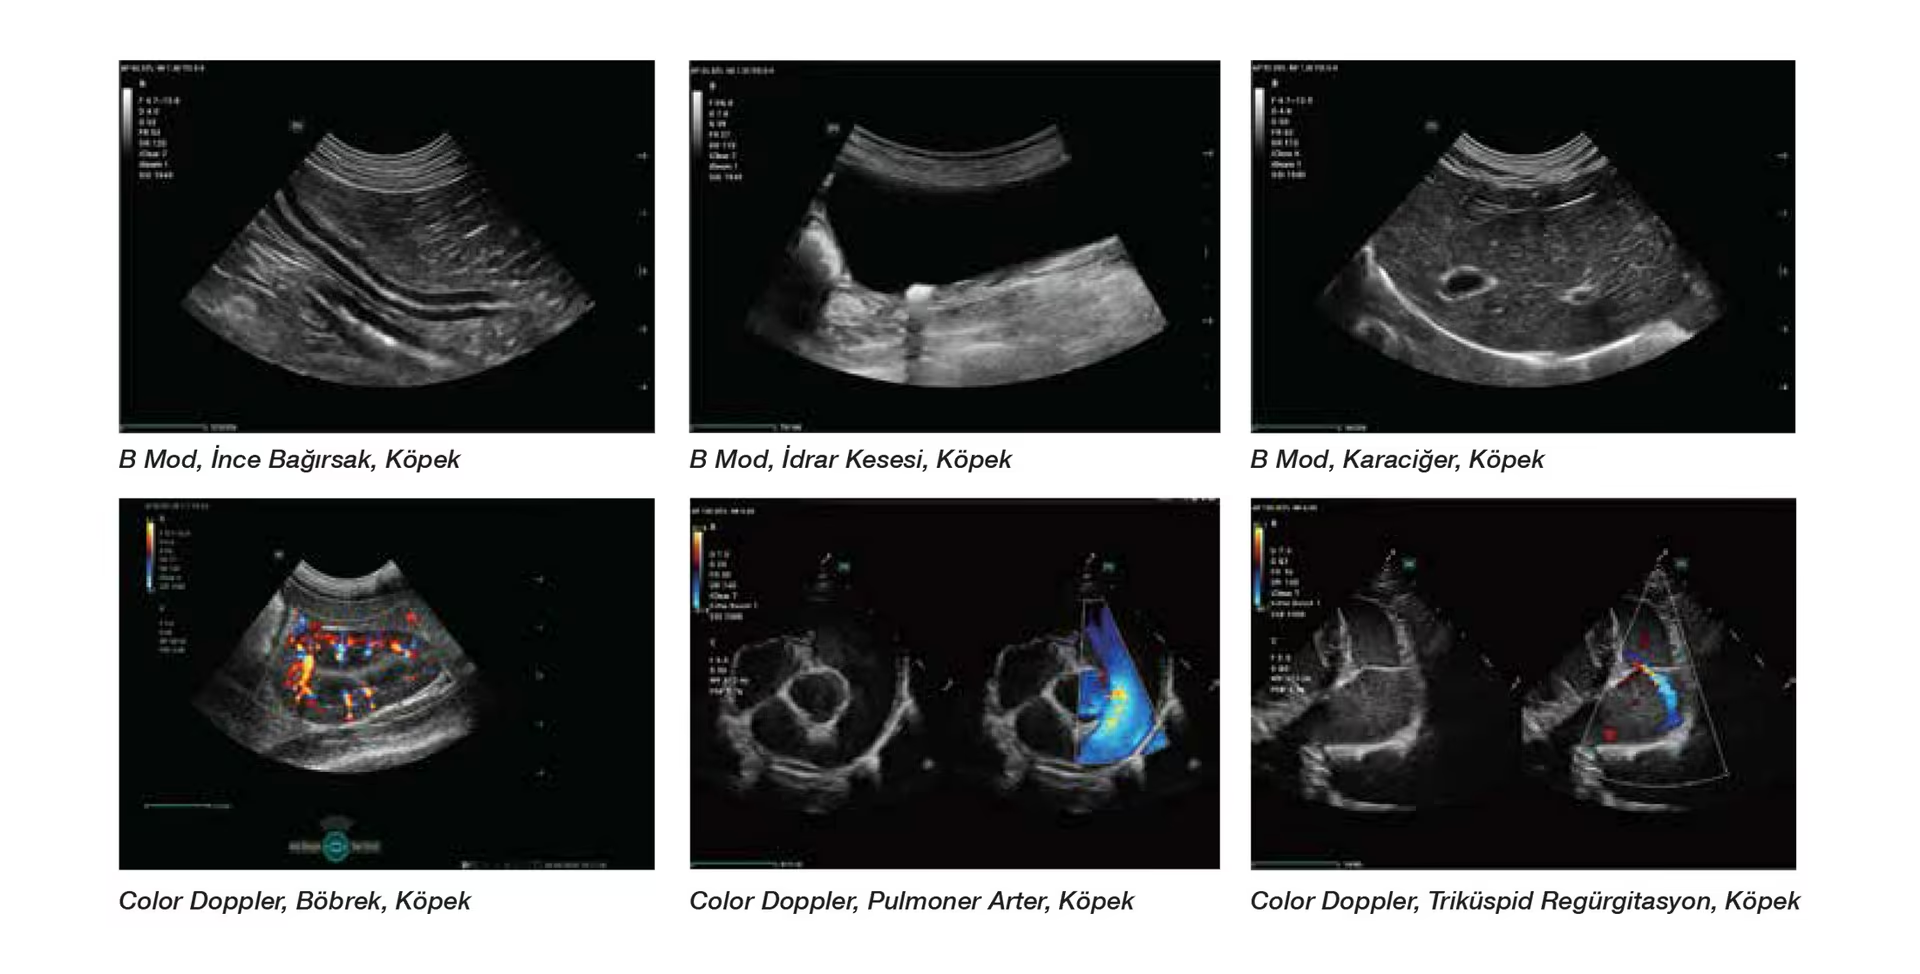

Vetus Nova prob serisi, tamamen 3T prob teknolojisini kullanmaktadır. Üç uyumlu katman, tam kesimli tasarım, termal kontrol teknolojisi sayesinde daha temiz sinyal elde edilir ve daha az sinyal kaybı ile daha net detaylar sağlanır. Bu sayede aynı anda hem güçlü penetrasyon hem de yüksek çözünürlük elde edilir.

Vetus NOVA, yenilikçi dönüştürücüleri ve gelişmiş görüntü işleme teknolojisiyle net hayvan ultrason görüntüleri sunar.

Vetus NOVA problarının tüm serisi 3T dönüştürücü teknolojisini benimser. Üçlü eşleştirme katman teknolojisi, toplam kesim tasarımı ve sıcaklık kontrol teknolojisi daha saf bir sinyal sağlar, gerçek görüntüleri geri yükler ve daha net ayrıntılarla daha az sinyal kaybı sağlar.